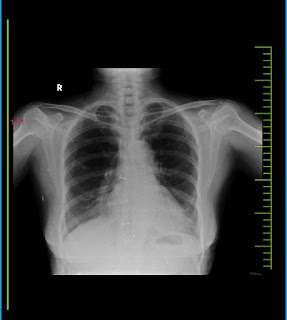

Chest X-Ray